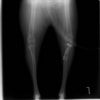

術前正面像

術後左後肢正面像

術前のTPAは左後肢33.1°右後肢26.8°でしたがTPLO実施により左後肢5.5°右後肢12°に矯正されました。